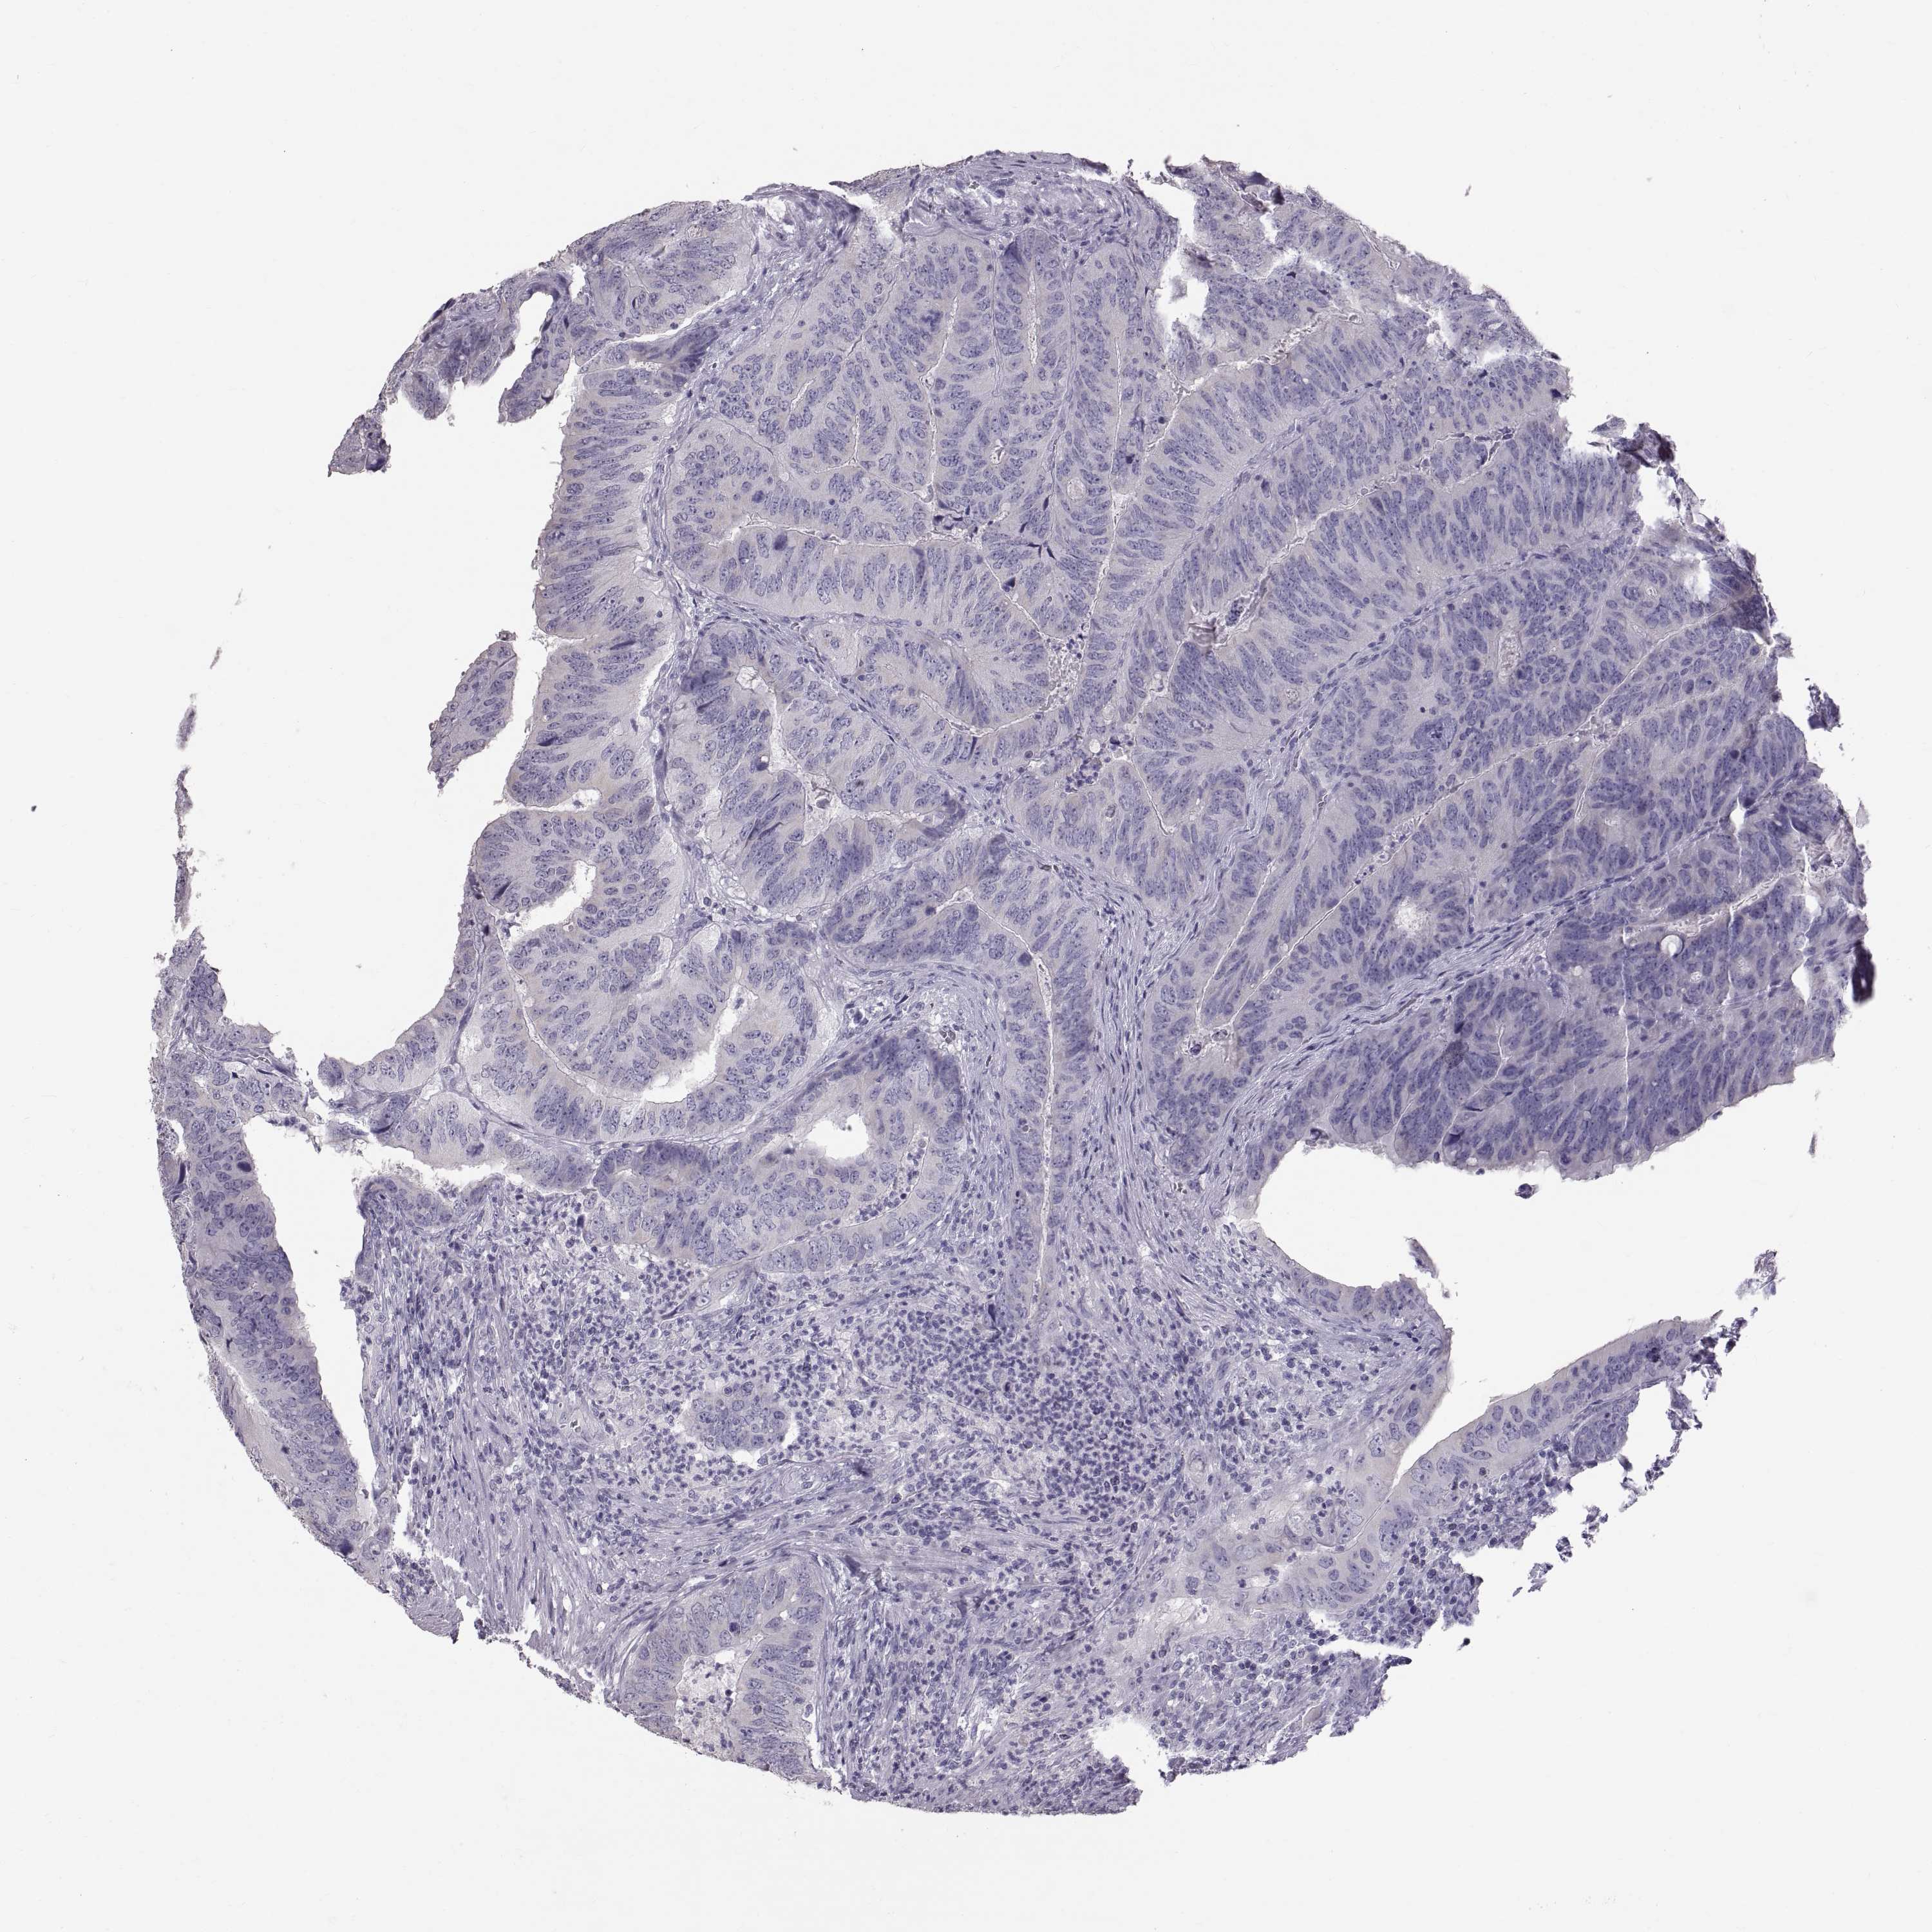

CANCER COLORECTAL CANCER Show tissue menu

Colorectal cancer

Colon adenocarcinoma